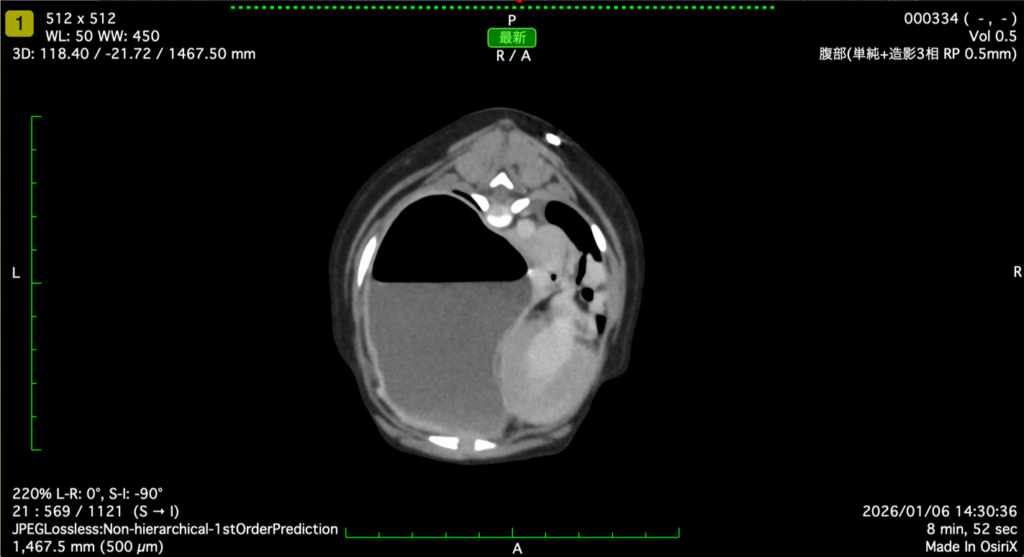

本症例は夜間に呼吸促迫と元気消失を主訴に紹介受診し、画像検査で原因精査を行いました。CT検査では胃が胸腔内へ脱出し、中等度に拡張して肺を強く圧排していました。また、左肺の虚脱と軽度の気胸がみられ、呼吸機能低下が懸念される所見でした。脾臓には造影増強の乏しい領域があり血流障害が疑われ、膵臓は不均一な造影増強と周囲脂肪の変化から浮腫/膵炎の併発にも注意が必要と判断しました。